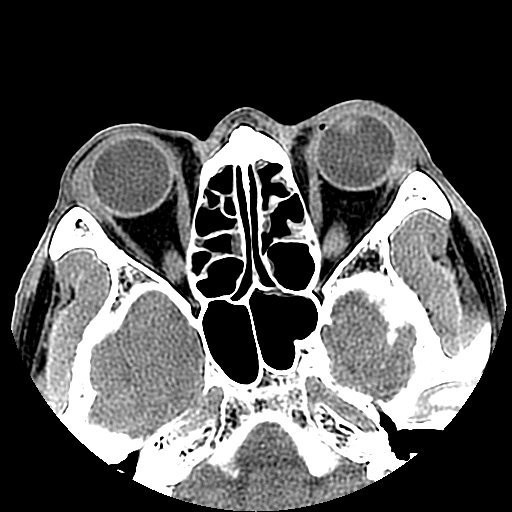

以下是引用liaoqiang在2008-7-16 21:15:00的发言:[br]右侧鼻骨骨折

以下是引用zxd95在2008-7-16 21:39:00的发言:[br]右侧上颌骨额突骨折。[br][br][br][br]